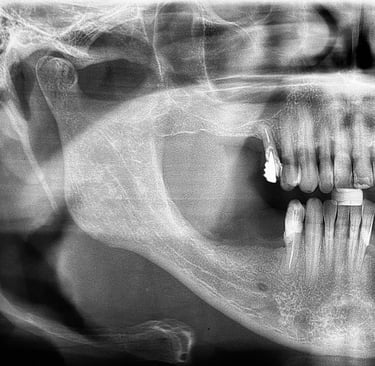

Implante feito por outro profissional há cerca de 5 anos desenvolveu inflamação, saída de pus e gengiva inflamada, indicando peri-implantite, uma infecção que pode comprometer o implante se não tratada.